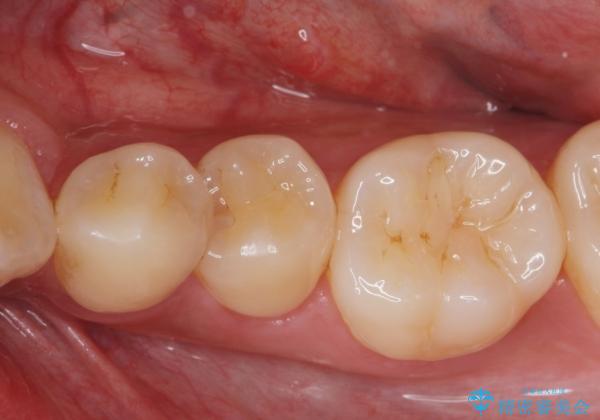

矯正前の虫歯治療

- 矯正前の患者様です。検査により虫歯がありましたのでe-maxインレー治療を行いました。

- e-maxインレー 7.7万×2費用は治療当時の料金となります

虫歯がある状態で矯正を始めてしまうと矯正治療中に虫歯が悪化してしまう可能性があります。